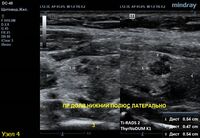

2) Узел у перешейка, не прорастает капсулу щитовидной железы (0 баллов), больше широкий чем высокий (0 баллов), не имеет кальцинатов (0 баллов), с ровным четким контуром (0 баллов), гипоэхогенный (2 балла), тканевой структуры (2 балла). Количество баллов 4, ACRTi-RADS4, ThyrNoDUMК6. Пункция не показана в связи с малым диаметром узла (более 1,5 см для Ti-RADS4), рекомендовано наблюдение.